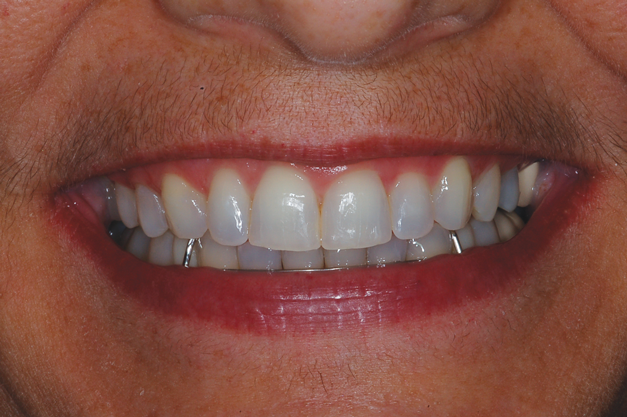

(14.) Smile photograph of the patient in Figure 13 immediately after removal of the arch wires and brackets, showing no white spot lesions or any yellow spots where the the bonded brackets were previously located.

Figure 14